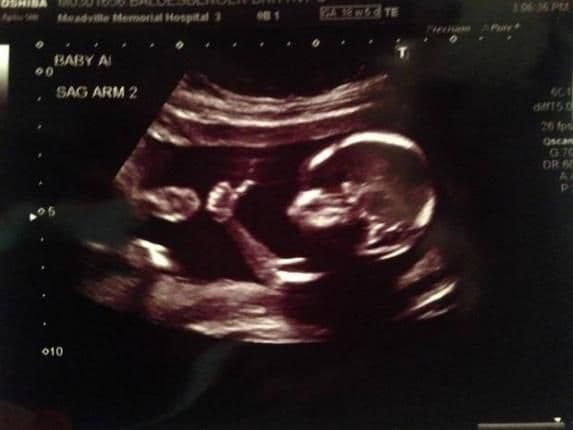

Dječak je držao uzdignut palac, kao da poručuje mami da je sve u redu i da ne mora da brine.

Slika je obišla internet, nakon što je na sajtu "Reddit" objavio oduševljeni budući otac.

Oni koji su vidjeli sliku sa ultrazvuka takođe su primijetili da razigrana beba nije sama. Majka je potvrdila da čeka blizance.